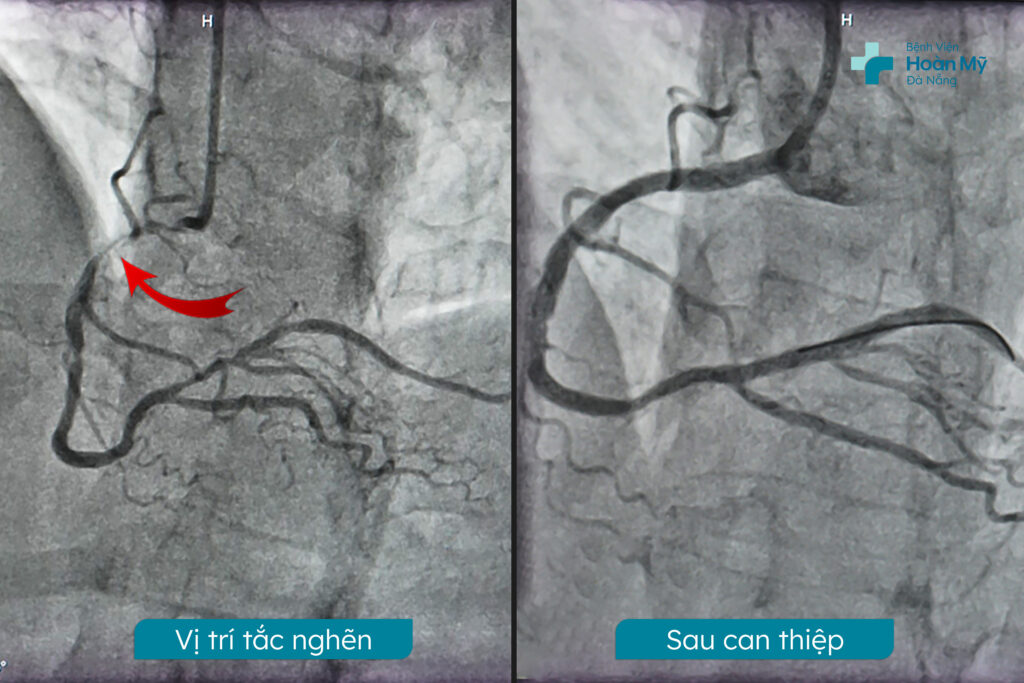

Kết quả chụp mạch vành qua da: tổn thương 3 nhánh mạch vành: hẹp nặng động mạch vành phải dòng chảy chậm, mạch mủ hẹp nặng nhiều vị trí cả lỗ vào, hẹp trung bình đoạn đầu liên thất trước từ ngay lỗ vào. Theo ý kiến chuyên khoa, trường hợp này sẽ có hai phương pháp điều trị: phẫu thuật mổ bắt cầu hoặc can thiệp nội mạch. Mỗi phương pháp đều có ưu điểm và rủi ro riêng. Sau khi được bác sĩ tư vấn kỹ lưỡng về cả hai phương pháp, gia đình người bệnh đã quyết định lựa chọn can thiệp nội mạch – không phải mở ngực hở và giúp phục hồi nhanh hơn.

Động mạch vành phải được tái thông bằng sten sau can thiệp

Bác sĩ đã tiến hành can thiệp động mạch vành phải bằng cách đặt hai stent phủ thuốc nhằm tái thông dòng chảy máu về trạng thái bình thường. Cơ thể bệnh nhân phản ứng tích cực với can thiệp, cho thấy tín hiệu khả quan. Sau thủ thuật, tình trạng sức khỏe của người bệnh đã được cải thiện rõ rệt và duy trì ổn định.

Kết quả thủ thuật thành công như mong đợi. Các tổn thương đoạn xa của động mạch mũ và đoạn I LAD được mở rộng lòng mạch bằng stent phủ thuốc. Vị trí chổ chia thân chung lựa chọn chiến lược kỹ thuật Mini Crush với 2 Stent phủ thuốc loại tốt. Các stent được đặt chính xác vào các vị trí tổn thương, giúp mở rộng lòng mạch và cải thiện lưu lượng máu đến tim.